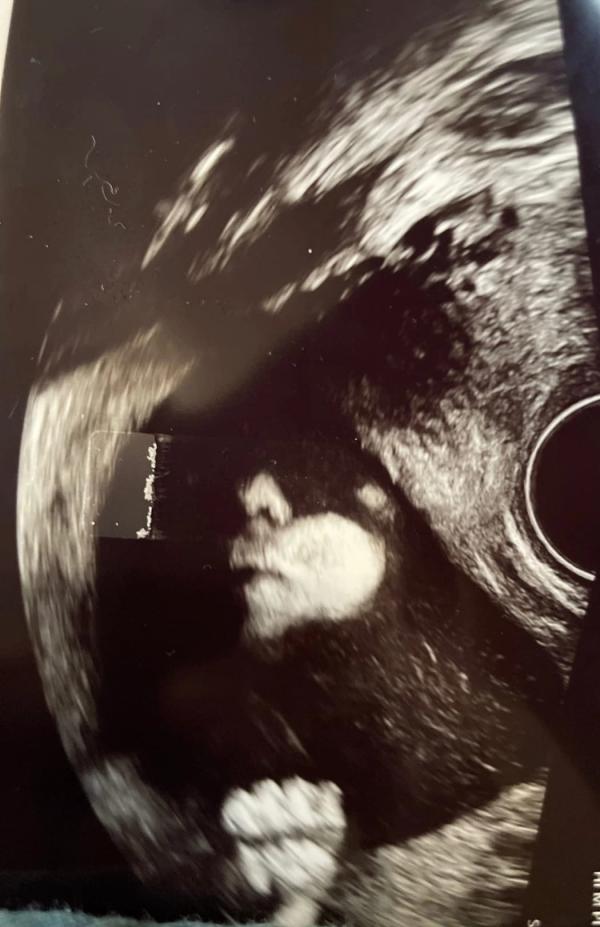

Сын сама серьёзность 🗿